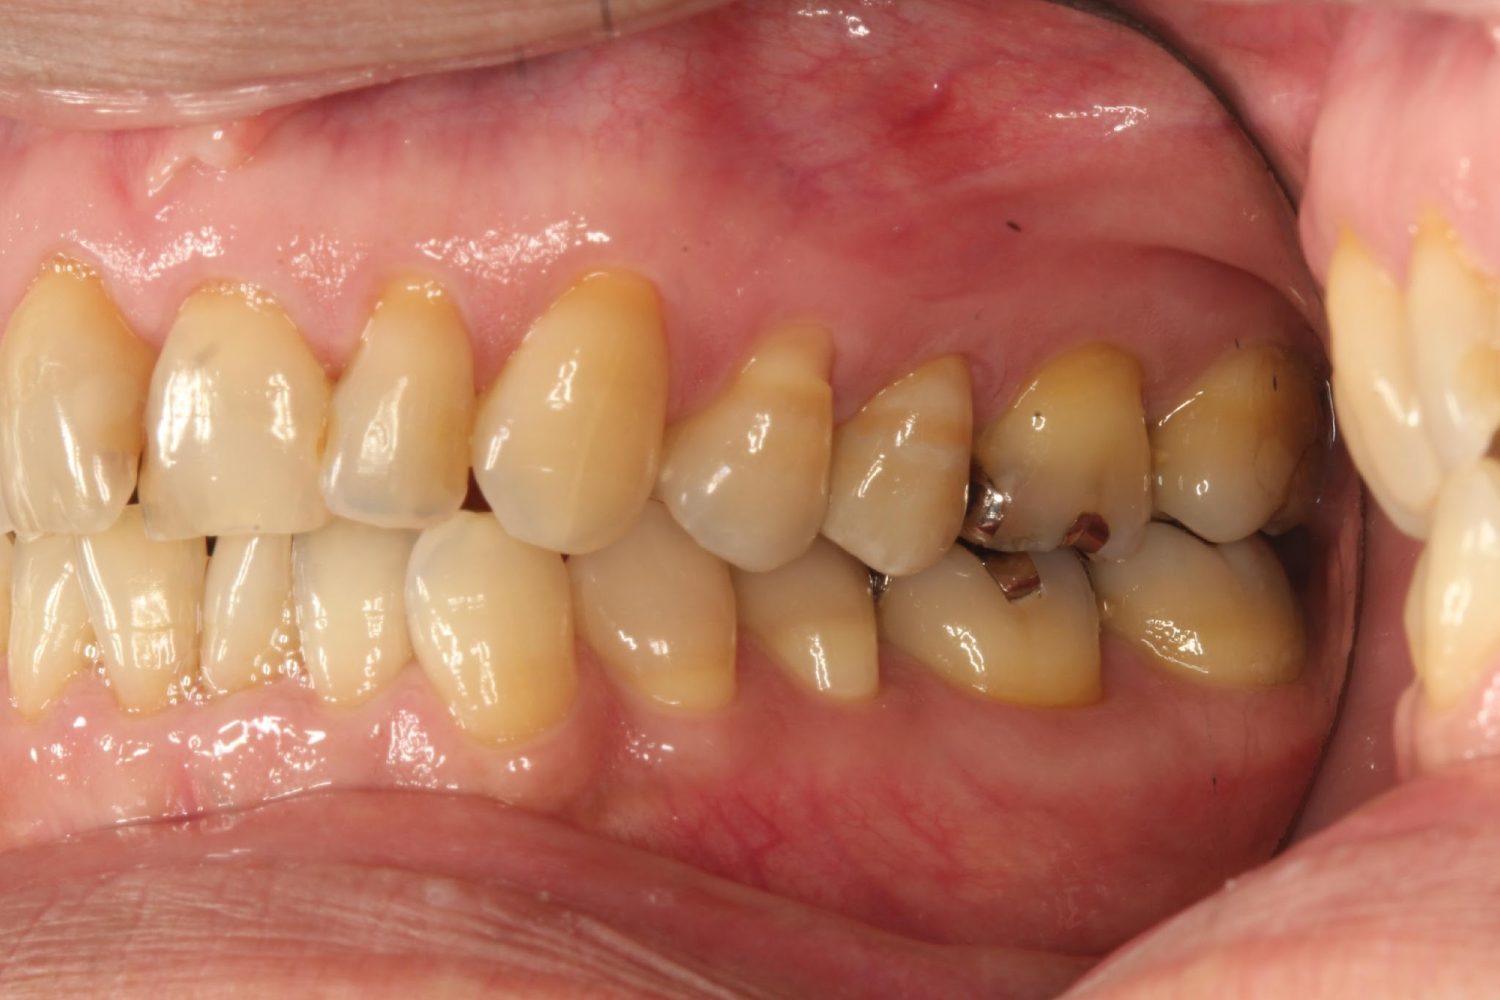

インプラント治療の症例紹介⑥

Before

After

主訴

咬めるようになりたい

治療内容

保存不可能な歯の抜歯、上下の咬み合わせを揃えて欠損部にインプラント治療

治療費

2,508,000円(税込)

治療期間

19ヶ月

通院回数

26回

想定されたリスク

※血糖値の高い方で、咬めるようになると高血糖となる可能性があるため食事制限が必要となる。インプラント周囲炎の恐れがありました。

濱 仁隆先生

浜歯科

歯の欠損による対合歯の挺出等を修正し咬合平面を揃えた症例